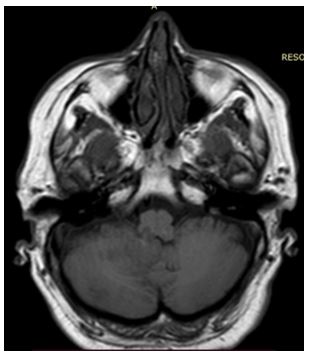

Se solicita resonancia magnética que reporta preservación de la sustancia gris-blanca, surcos, cisuras y espacios de amplitud normal, se observan lesiones hiperintensas en la sustancia blanca profunda en secuencias T2 y FLAIR correspondiente a zona del flóculo principalmente derecho, vermis y parte posteromedial de lóbulo cerebeloso posterior derecho y posterior izquierdo, además de zonas de malasia en ambos hemisferios cerebelosos.

Imagen 3, 4 y 5: Secuencia FLAIR con lesiones hiperintensas correspondiente a zona del flóculo principalmente derecho, vermis y parte posteromedial de lóbulo cerebeloso posterior derecho y posterior izquierdo.

Imagen 6, 7 y 8: Secuencia T2 con lesiones hiperintensas correspondiente a zona del flóculo principalmente derecho, vermis y parte posteromedial de lóbulo cerebeloso posterior derecho y posterior izquierdo.